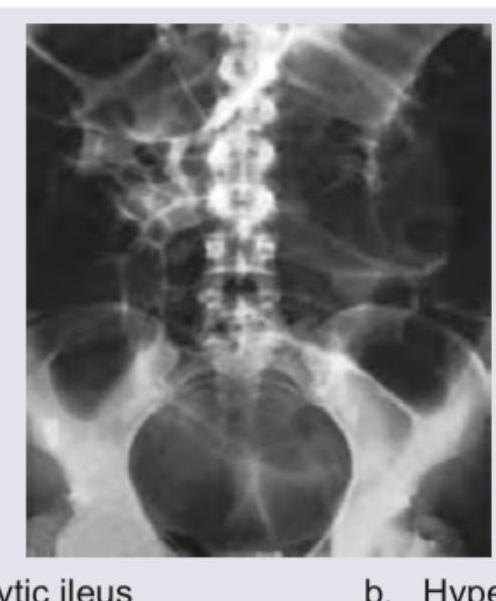

Explanation: ***Uric acid*** - The X-ray KUB image shows **radio-lucent stones** (stones that are not visible) within the kidneys, which is characteristic of **uric acid** stones. - Uric acid stones appear radio-lucent because they **do not contain calcium** and have a low atomic number, making them poorly visible on plain radiographs. *Xanthine* - **Xanthine stones** are also typically **radio-lucent** on X-ray, similar to uric acid stones. - However, they are much **rarer** than uric acid stones, often associated with genetic disorders of purine metabolism or allopurinol use. *Phosphate* - **Phosphate stones**, such as **calcium phosphate** and **magnesium ammonium phosphate (struvite)** stones, are typically **radio-opaque** and appear bright white on X-ray. - Struvite stones often grow large, forming **staghorn calculi**, which is not depicted as a radio-opaque lesion here. *Cystine* - **Cystine stones** are usually **faintly radio-opaque** or **semi-opaque** on X-ray, appearing less dense than calcium stones but more dense than uric acid stones. - They tend to form in acidic urine environments due to a genetic defect in amino acid transport.

Explanation: ***Paralytic ileus*** - The image shows a **plain abdominal radiograph** revealing **diffusely dilated bowel loops** throughout the small and large intestines, with air-fluid levels, consistent with **paralytic ileus** (also known as adynamic ileus). - Paralytic ileus is a common cause of bowel dilation post-surgery, inflammation, or electrolyte disturbances, where **peristalsis ceases temporarily** without a mechanical obstruction. *Hyperkalemia* - **Hyperkalemia** is an electrolyte imbalance that can lead to significant cardiac dysfunction and muscle weakness, but it **does not directly cause generalized bowel dilation** visible on an X-ray. - While severe electrolyte imbalances can sometimes contribute to ileus, hyperkalemia itself is a metabolic derangement, not a radiographic finding. *Burst abdomen* - A **burst abdomen** (or wound dehiscence) refers to the **separation of abdominal wound edges**, typically after surgery, and is a clinical finding, often with evisceration. - It describes a **surgical complication of the abdominal wall** and is not reflected by the dilated bowel loops seen internally on this radiograph. *Malnutrition* - **Malnutrition** is a state of nutrient deficiency and can lead to various systemic problems, including muscle wasting and immune compromise. - While severe malnutrition can subtly affect bowel function over time, it is **not directly demonstrable as acute, diffuse bowel dilation** on a plain abdominal X-ray.